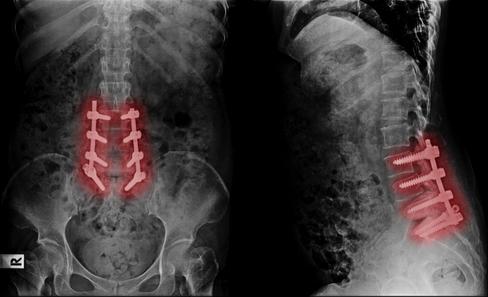

Back Pain should not mean fusion,

Back Pain should not mean fusion, screws, and lengthy recoveries Regenerative Medicine is changing how back pain is solved.

Back Pain should not mean fusion, screws, and lengthy recoveries. Regenerative ng how back pain is solved